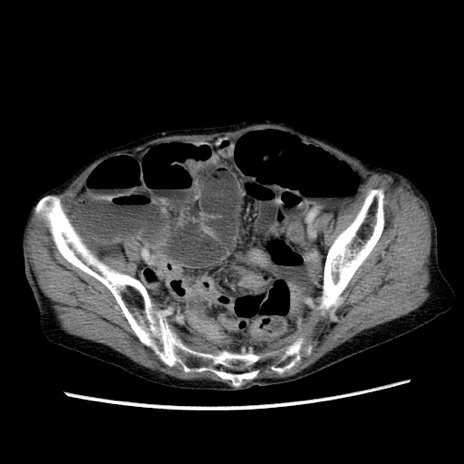

症例25(横断像)

【症例】80歳代女性

【主訴】胸のつかえ感

【現病歴】約9時間前に食後から胸のつかえた感じあり、嘔吐あり、来院。

【既往歴】胃癌(全摘)、胆摘、虫垂炎

【身体所見】心窩部に圧痛あり、反跳痛なし。

【データ】WBC 5700、CRP 0.05